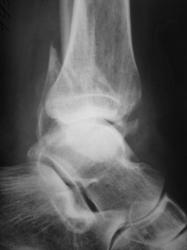

Перелом обеих лодыжек со смещением, наружно-пронационный вывих стопы.

А передний край пилона разве не сломан? Или это медиальная лодыжка наслаивается?